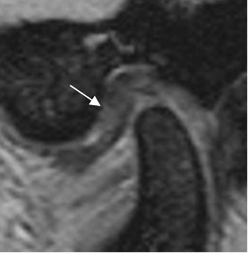

El hallazgo mas frecuente es el desplazamiento anterior del disco. (2). La banda posterior se localiza por delante del cóndilo y al abrirla boca, se produce un chasquido, que corresponde a la reacomodación o reducción. Con la progresión de la alteración, no se produce la reducción. (Fig 7, 8 y 9).

Fig 7. Disco luxado.

RM GE sagital oblicuo con boca cerrada. Desplazamiento anterior del disco. Banda anterior. (Flecha delgada).